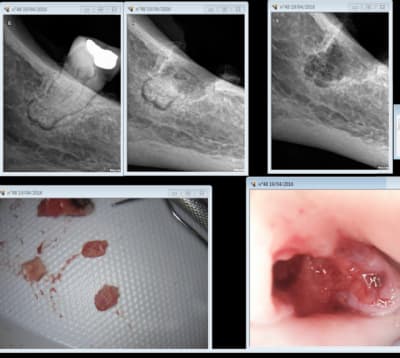

Patiente 50 ans, aucun pb de sante qui est partie aux urgences en cours d extraction de 38 chez son dentiste.

Transfusion de 2 litres de sang!!!

ouf, tout s est bien passe, ils ont eut juste du mal a l endormir tellement elle etait stressee.

Racines sorties en 10 minute et lambeau uniquement mesial et buccal.

on voyait l artere fautive en distal de la 38.

Situation anatomique exceptionnelle, elle se baladait le long du Canal mandibulaire et venait flirter en distal de la 38.

Malheureusement le dentiste a file un coup de fraise dedans.

Vraiment pas de chance.

Il a eut du bol que le saignement soit externe et vienne pas se coincer dans le plancher buccal, car la c est 30 minutes max..

Pas sur qu'un cone beam l'aurait mise en évidence.

Si le cbct l a mise en evidence par le radiologue dentaire, mais c est vraiment exceptionnel 1/10000